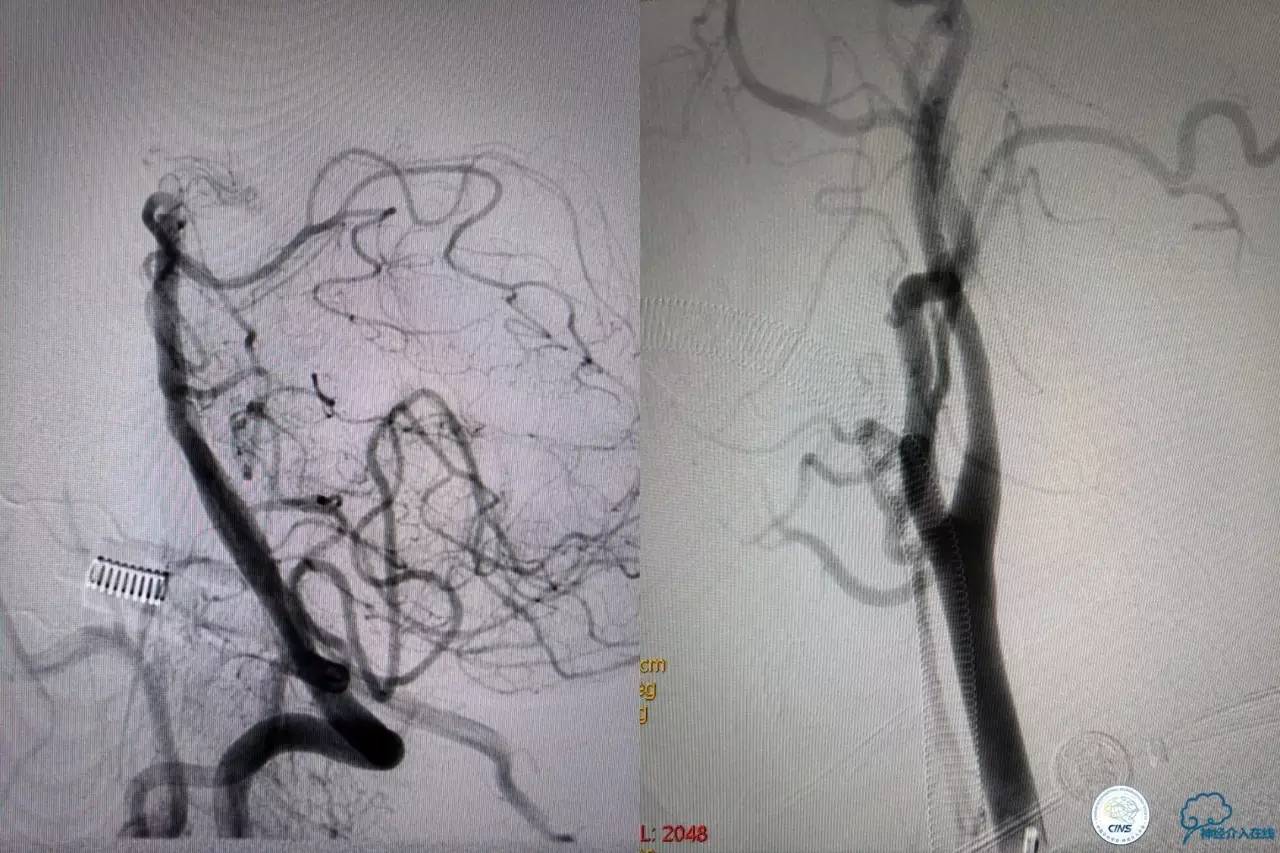

造影结果:右侧颈总动脉远端闭塞,前交通动脉开放,代偿方式:左侧颈内动脉→左侧大脑前动脉A1→前交通动脉→右侧大脑前动脉A1(反向)→右侧大脑中动脉供血区代偿。双侧大脑后动脉、右侧小脑上动脉及基底动脉顶端未见显影。

结合病史,体征及影像学,考虑患者本次发病为基底动脉尖急性闭塞,发病机制:栓塞?右侧颈总动脉慢性闭塞?非责任血管,且代偿良好,暂时不需处理!

6F导引导管到位至RV2远端,rebar-18微导管及transand微导丝至右侧大脑后动脉P1远端。

solitaireAB4-20mm支架取栓。